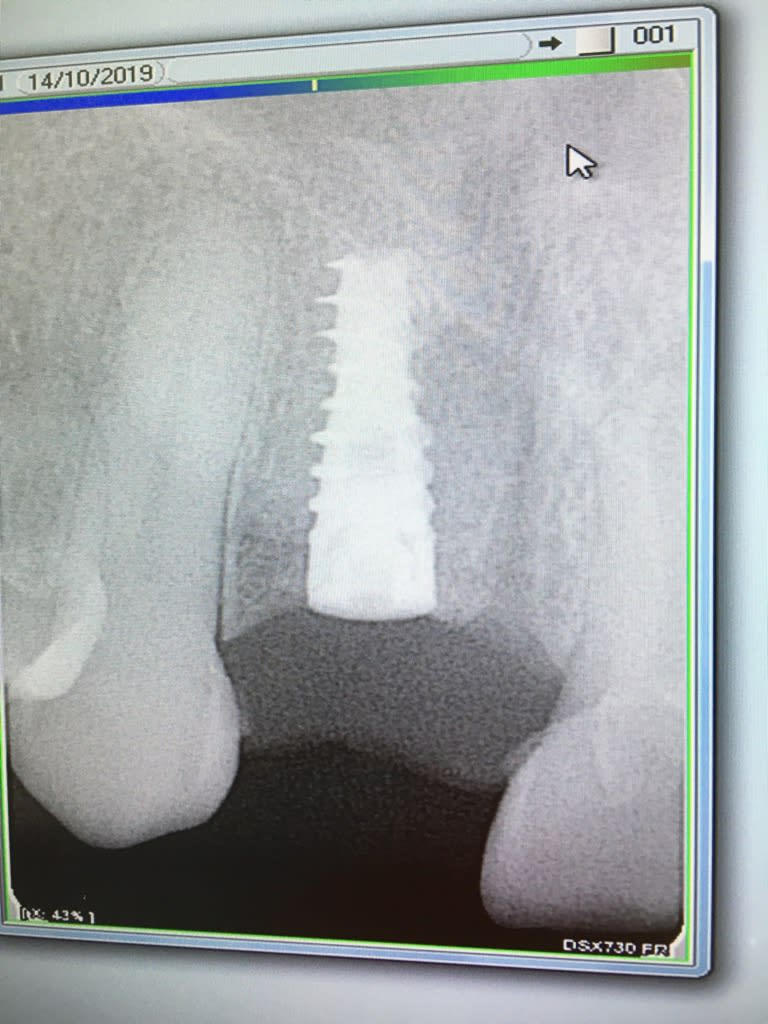

Bonjour, si vous avez une idée! Merci

SPI Alphabio

http://osseosource.com/dental-implants/product_info.php?manufacturers_id=18&products_id=59

Attention pour le coup Pluton, le Brat Implant est à s'y méprendre. Il faut voir la forme du col. Pour un les strie sont penchées (Alpha) l'autre elles sont parallèles (Brat) c'est radiologiquement la seule différence visible pour moi.

oui mais on s'en bat les c.... c'est la même connexion type "zimmer", çà peut aussi être un TOV d'ailleurs, mais çà change rien au final:

connexion zimmer classique, tournevis 1.25mm torque de vissage 30Ncm et voilà...;-)